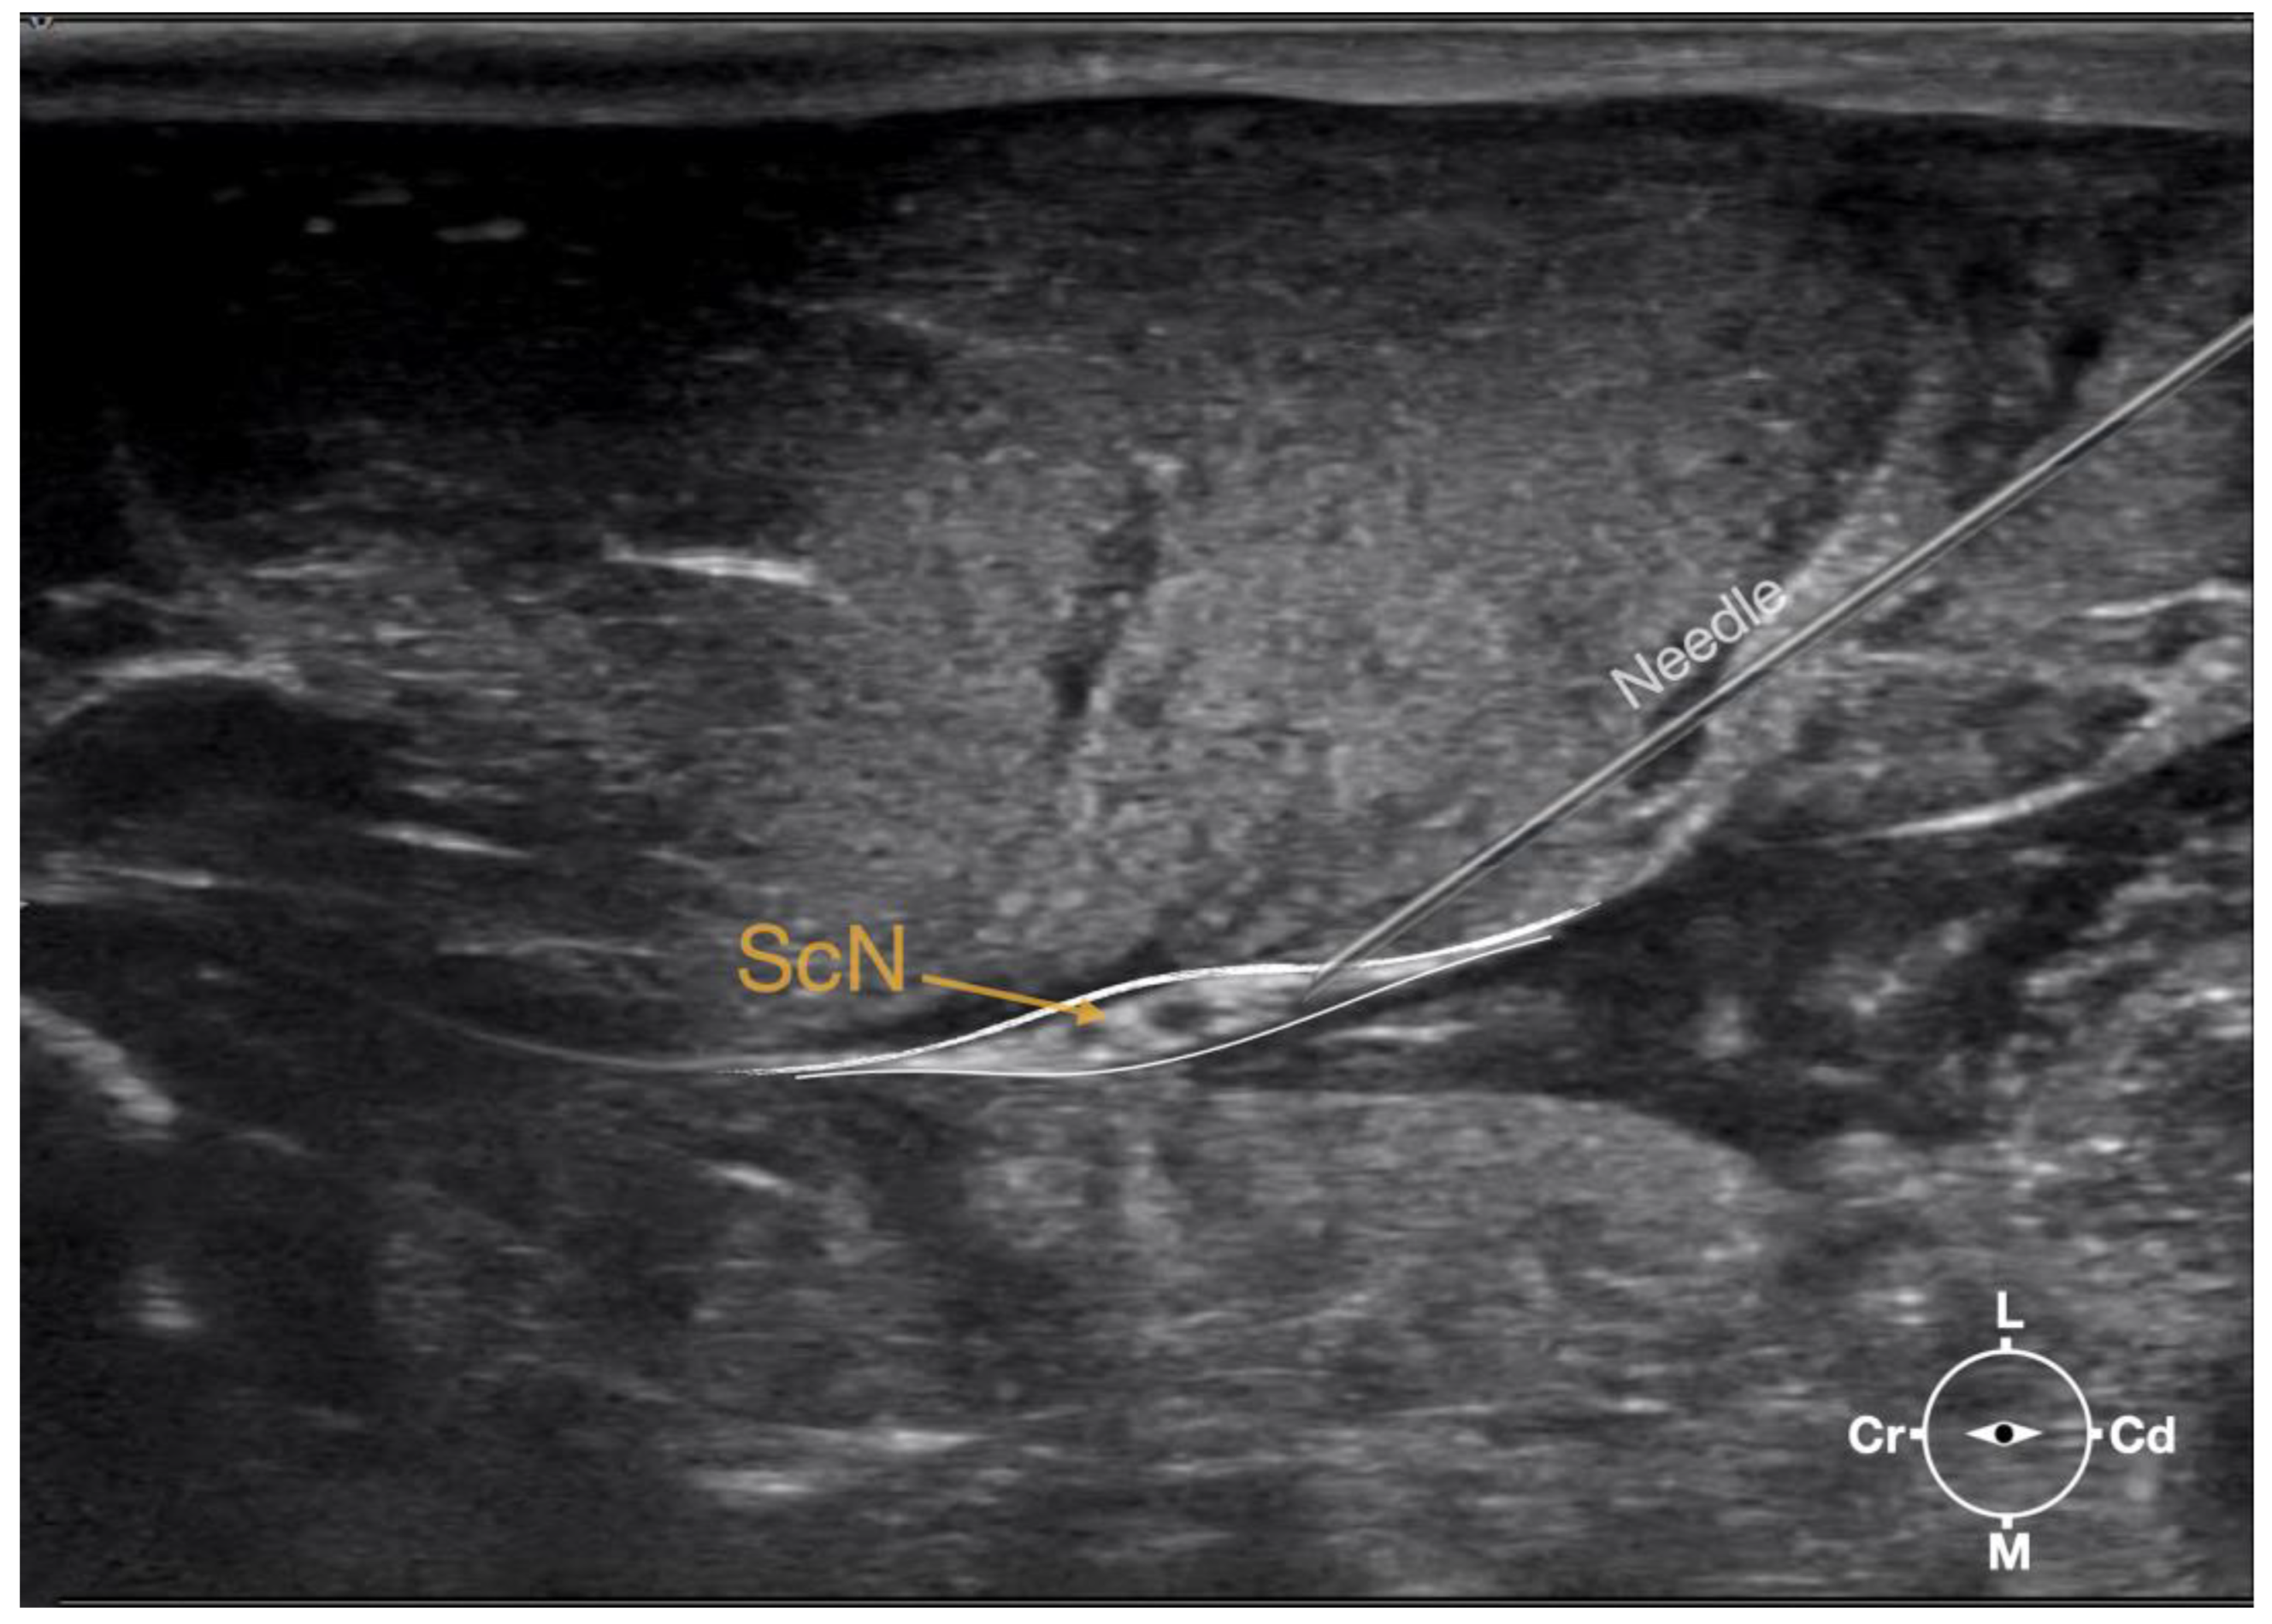

Figure 3.

Ultrasonographic image demonstrating the approach of the needle towards the sciatic nerve. Depth at 3 cm and focus on the level of the nerve. ScN, sciatic nerve; Cr, cranial; Cd, caudal; L, lateral; M, medial.

First, the cadaver was positioned in lateral recumbency. Then, the area of interest was clipped. A 18-4 MHz linear transducer (L 18-4, Konica Minolta, Ramsey, NJ, USA) attached to an ultrasound machine (HS1, Konica Minolta, USA) was used and ultrasound gel (Softa-Man, ViscoRub, B. Braun, Maria Enzersdorf, Austria) was applied to facilitate acoustic coupling. The transducer was placed in transverse position, at the level of the proximal third of the femur but caudal to the bone with a window of interest set at a depth of 3 cm to optimize the image. Then, the transducer was slightly rotated clock or anticlockwise to obtain a transverse image of the sciatic nerve (Figure 1). A 50 mm 22-gauge insulated needle (Sonoplex Stim Cannula, Pajunk Medical Produkte GmbH, Geisingen, Germany) prefilled with a solution of L-NMB was inserted using an in-plane approach. The needle was inserted at the caudal end of the transducer and advanced in-plane under sonographic guidance through the biceps femoris muscle in a cranio-medial direction towards the sciatic nerve (Figure 2). The needle was advanced until its tip punctured the muscular fascia enveloping the sciatic nerve (Figure 3). A test volume of 0.05 mL of L-NMB was injected to confirm adequate distribution inside the interfascial space that contained the sciatic nerve. The remaining volume of 0.15 mL/kg was then injected perineurally around the sciatic nerve.

Ultrasonographically, the sciatic nerve appeared as a binocular structure with a hyperechoic rim surrounded by the muscular fascias of the biceps femoris and adductor muscles at this level. All muscles were displayed as structures with heterogeneous echogenicity. The biceps femoris muscle was lying lateral to the ScN while the adductor muscle was medial to the ScN. The femur was displayed as a hyperechoic structure with acoustic shadow and located cranial to the ScN nerve.